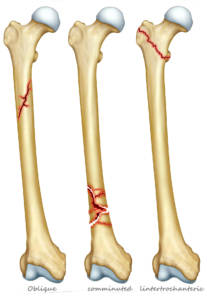

Dove si riscontrano le fratture da osteoporosi

In tutto lo scheletro si possono riscontrare fratture da osteoporosi, ma quelle più frequenti sono:

- all’estremità prossimale del femore, in zona inguinale;

- all’estremità distale del radio, cioè al polso;

- sulle vertebre, lungo la colonna dorso lombare;

- all’estremità prossimale dell’omero, in zona ascellare;

- alle anche, intorno al bacino.

Attenzione: perché il femore può subire ulteriori fratture dopo la prima: nei successivi 5 anni dalla prima frattura le probabilità di subirne una nuova salgono al 20%. E le possibilità che venga colpito da frattura il femore della gamba opposta salgono al 50%. Spesso la frattura al femore può richiedere una lunga degenza.

Il femore è l’osso più lungo e resistente dello scheletro. È situato fra l’anca e il ginocchio e vi si inseriscono molti muscoli fondamentali per il movimento della gamba.

La sua resistenza può però ridursi con l’invecchiamento e può fratturarsi a livello del collo per minimi traumi o anche in loro assenza.